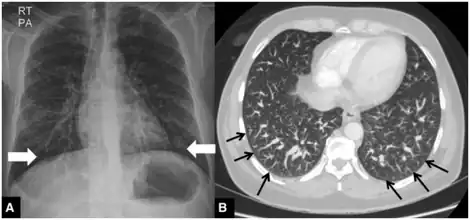

| a) Hepatopulmonary syndrome type 1 b) dilated distal pulmonary arteries | |